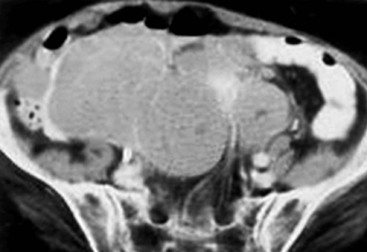

Lymphangioma represents a congenital malformation of the lymphatic vessels arising from the bowel. The typical imaging appearance is that of a large, thin-walled, single or multiloculated cystic mass, with contents of water-to-fat attenuation on CT (Fig. 30-4) and of high signal intensity on T2-weighted MR images. Enhancement of the cyst wall and septa is seen. It is frequently closely associated with the small bowel. US is helpful in demonstrating the internal septations of the cystic mass.8

Large mesenteric lymphangiomas can be differentiated from ascites by the presence of septa, compression on adjacent intestinal loops and lack of fluid in the dependent peritoneal recesses.